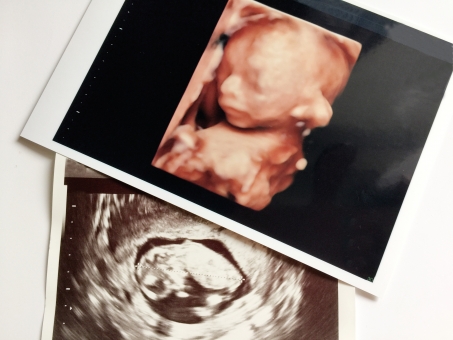

しかし妊娠30週目で胎児の胎動が無くなった時は、万が一で何かお腹の胎児にトラブルが起きている可能性もゼロではありません。胎動がなくなったことが気になる方は次の妊婦健診を待たずにかかりつけの医師の診察を受けてエコー検査などを実施してみても良いかもしれませんね。

妊娠30週目のお腹の胎児の大きさは気になるお母さんも多いと思います。妊娠30週目のお腹の胎児の大きさはエコー検査で見ると400ミリから500ミリぐらいに成長しています。400ミリから500ミリとは40センチから50センチほどですね。

胎児の大きさが平均以上に小さくても、また逆に平均以上に大きくても、きちんと妊婦健診を受けエコー検査などで毎回胎児の様子を確認している場合は、医師から特に指摘がなければ身体機能に全く問題はありません。